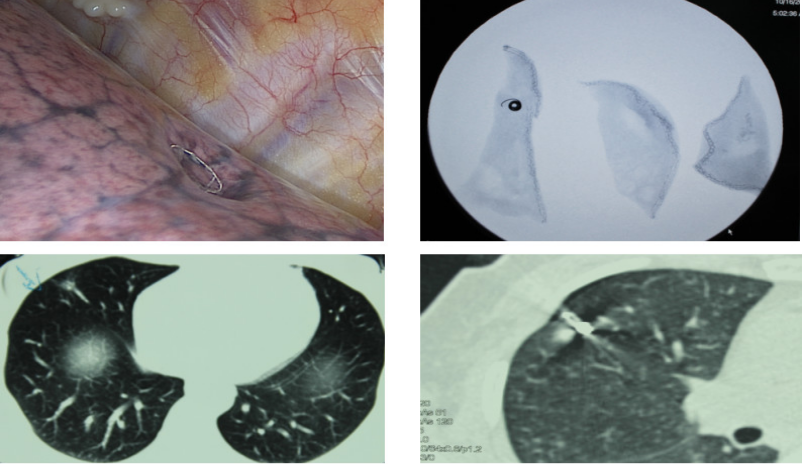

2、肺结节的术前术中定位方式

术前定位有CT 引导下经皮肺穿刺亚甲蓝注射、放置微弹簧圈、Hook-Wire 定位、放射性示踪剂注射;经电磁导航支气管镜引导注入染色标志物或微弹簧圈等(费用贵)。术中定位有术中胸腔镜 B 超探头定位、术中CT定位。但是术前定位存在许多缺点如定位不准确、移位、出现血气胸等并发症,尚需密切注意并需进一步研究完善。

图九 CT引导下弹簧圈(Microcoil)定位